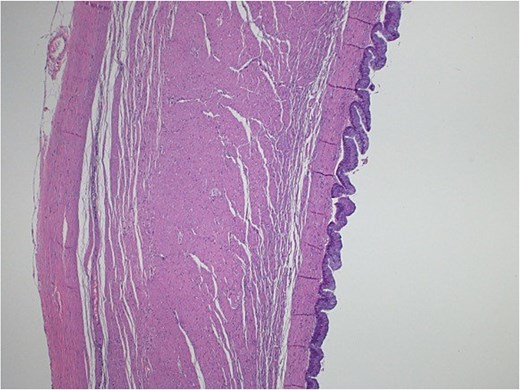

Light microscopy images of the appendix show low-grade dysplastic epithelium on the surface of the appendix (hematoxylin and eosin stain; 10×).